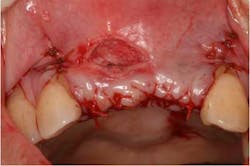

Fig. 11